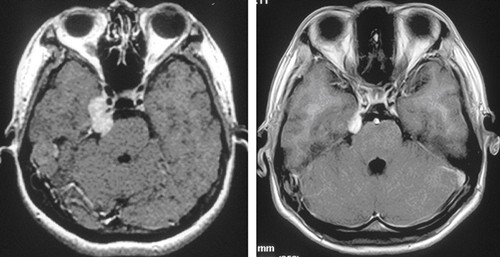

三叉神经鞘瘤给患者健康造成很大的危害,出现包括头痛、单侧面肌痉挛、听觉障碍、局灶性癫痫、偏瘫、步态异常、耳痛等症状。所以一定要及时去医院进行检查治疗。

(2)分组 五组分别为后颅窝肿瘤;三叉神经节肿瘤;哑铃状和幕下前方的肿瘤;外周分支的神经瘤;多颅窝的肿瘤(颅中窝和颅后窝,或颅中窝、颅后窝及颅外)。约36%~59%的三叉神经鞘瘤累及多个颅窝。